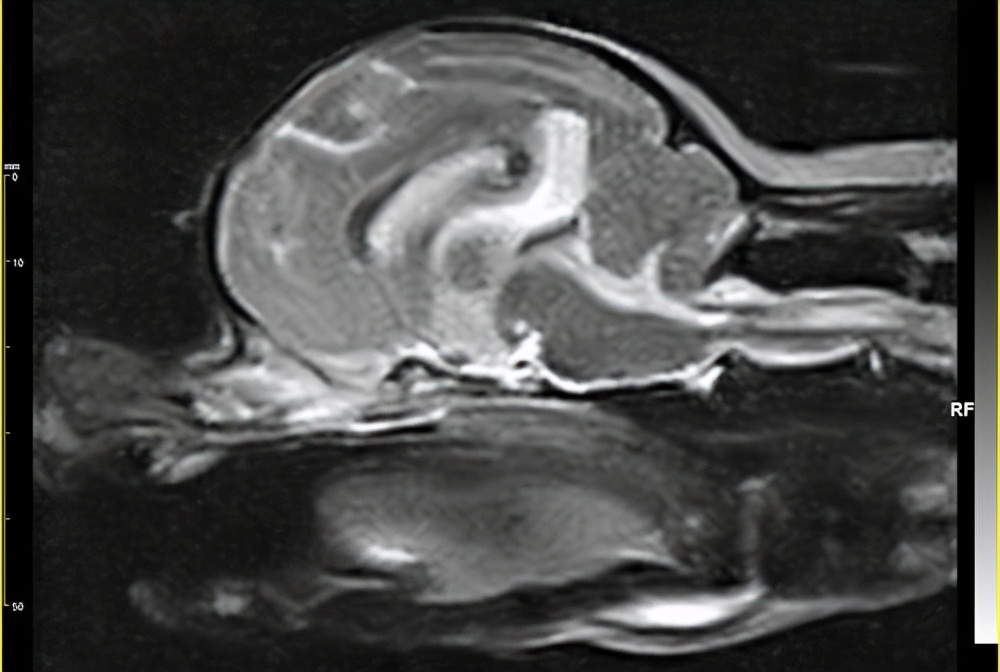

临床上使用的比较少,有一定的局限性。位于颅骨的肿瘤,一般可以采取CT检查,以及MRI检查,可以明确的诊断上颈区枕骨大孔、脊髓肿瘤,并可清楚显示肿瘤邻近延髓、颈髓及椎动脉及小脑后下动脉。舌下型神经瘤 CT表现为桥小脑角占位性增强扫描。

4、CT和MRI检查

尤其是 MRI对枕骨孔和上颈脊髓肿瘤的诊断具有重要意义。CT检查可以显示肿瘤以及椎动脉,以及延髓等和小脑后下动脉的关系。